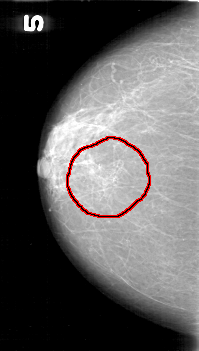

D_4136_1.RIGHT_MLO

RIGHT_MLO LINES 5371 PIXELS_PER_LINE 3121 BITS_PER_PIXEL 12 RESOLUTION 43.5 OVERLAY

FILE: D_4136_1.RIGHT_MLO.OVERLAY

TOTAL_ABNORMALITIES 1

ABNORMALITY 1

LESION_TYPE CALCIFICATION TYPE FINE_LINEAR_BRANCHING DISTRIBUTION SEGMENTAL

ASSESSMENT 4

SUBTLETY 3

PATHOLOGY MALIGNANT

TOTAL_OUTLINES 1

BOUNDARY